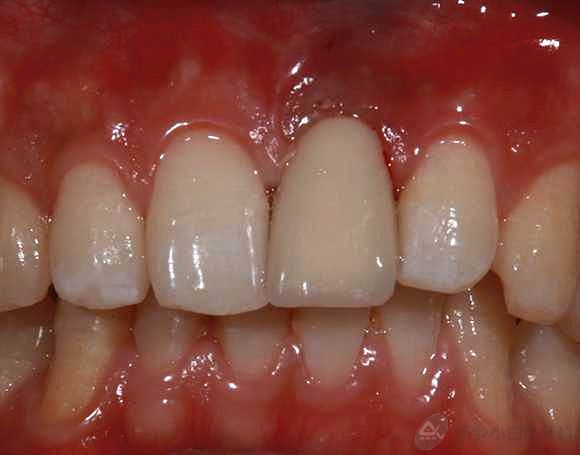

5.jpg

治疗后

2015年8月16号二期修复结束。